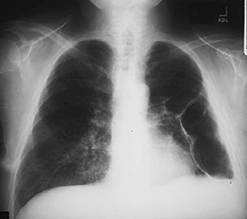

A 34-year-old amateur spelunker develops cough, dyspnea, and fever 2 weeks after a caving expedition to caves in Kentucky. On physical examination, the patient's temperature is 102°F and respiratory rate is 24. On pulmonary examination, there are diffuse crackles bilaterally. A CXR is shown in Figure .

The patient has diffuse interstitial infiltrates on CXR that correspond in time and presentation to acute inhalation histoplasmosis. This would be seen in a patient, such as an amateur spelunker, who has been in a cave with bats. It is the act of crawling through the cave that disturbs the spores of histoplasmosis that grow in the bat guano. The incubation period for influenza is 12 days. It is passed primarily by secretions from the nose spread by hands. The other members of the expedition were not sick, as they might be with influenza. Disseminated aspergillosis occurs in immunocompromised patients who have defects in both cell-mediated and humoral immunity. This patient does not have this. While the CXR could mimic military tuberculosis, the association with caving 14 days before would make tuberculosis less likely and histoplasmosis more likely. There is no history that the patient is immunocompromised with HIV and would be at risk for P. jiroveci pneumonia. Fungal serologies would establish the diagnosis, but acute and convalescent serologies would take 3 weeks for results. These are only useful in outbreak investigations. The other choices do not fit due to the reasons above. Treatment of acute respiratory histoplasmosis is based on severe hypoxia and would require arterial blood gases to establish the need for therapy. None of the fungal infections mentioned are transmissible person to person, therefore respiratory isolation would not be necessary. Histoplasmosis is a dimorphic fungus that grows as a yeast at body temperature and a mold at room temperature. The mold produces the spores that are infectious. A similar situation occurs for Cryptococcus neoformans. C. immitis and aspergillosis are not transmitted from person to person.